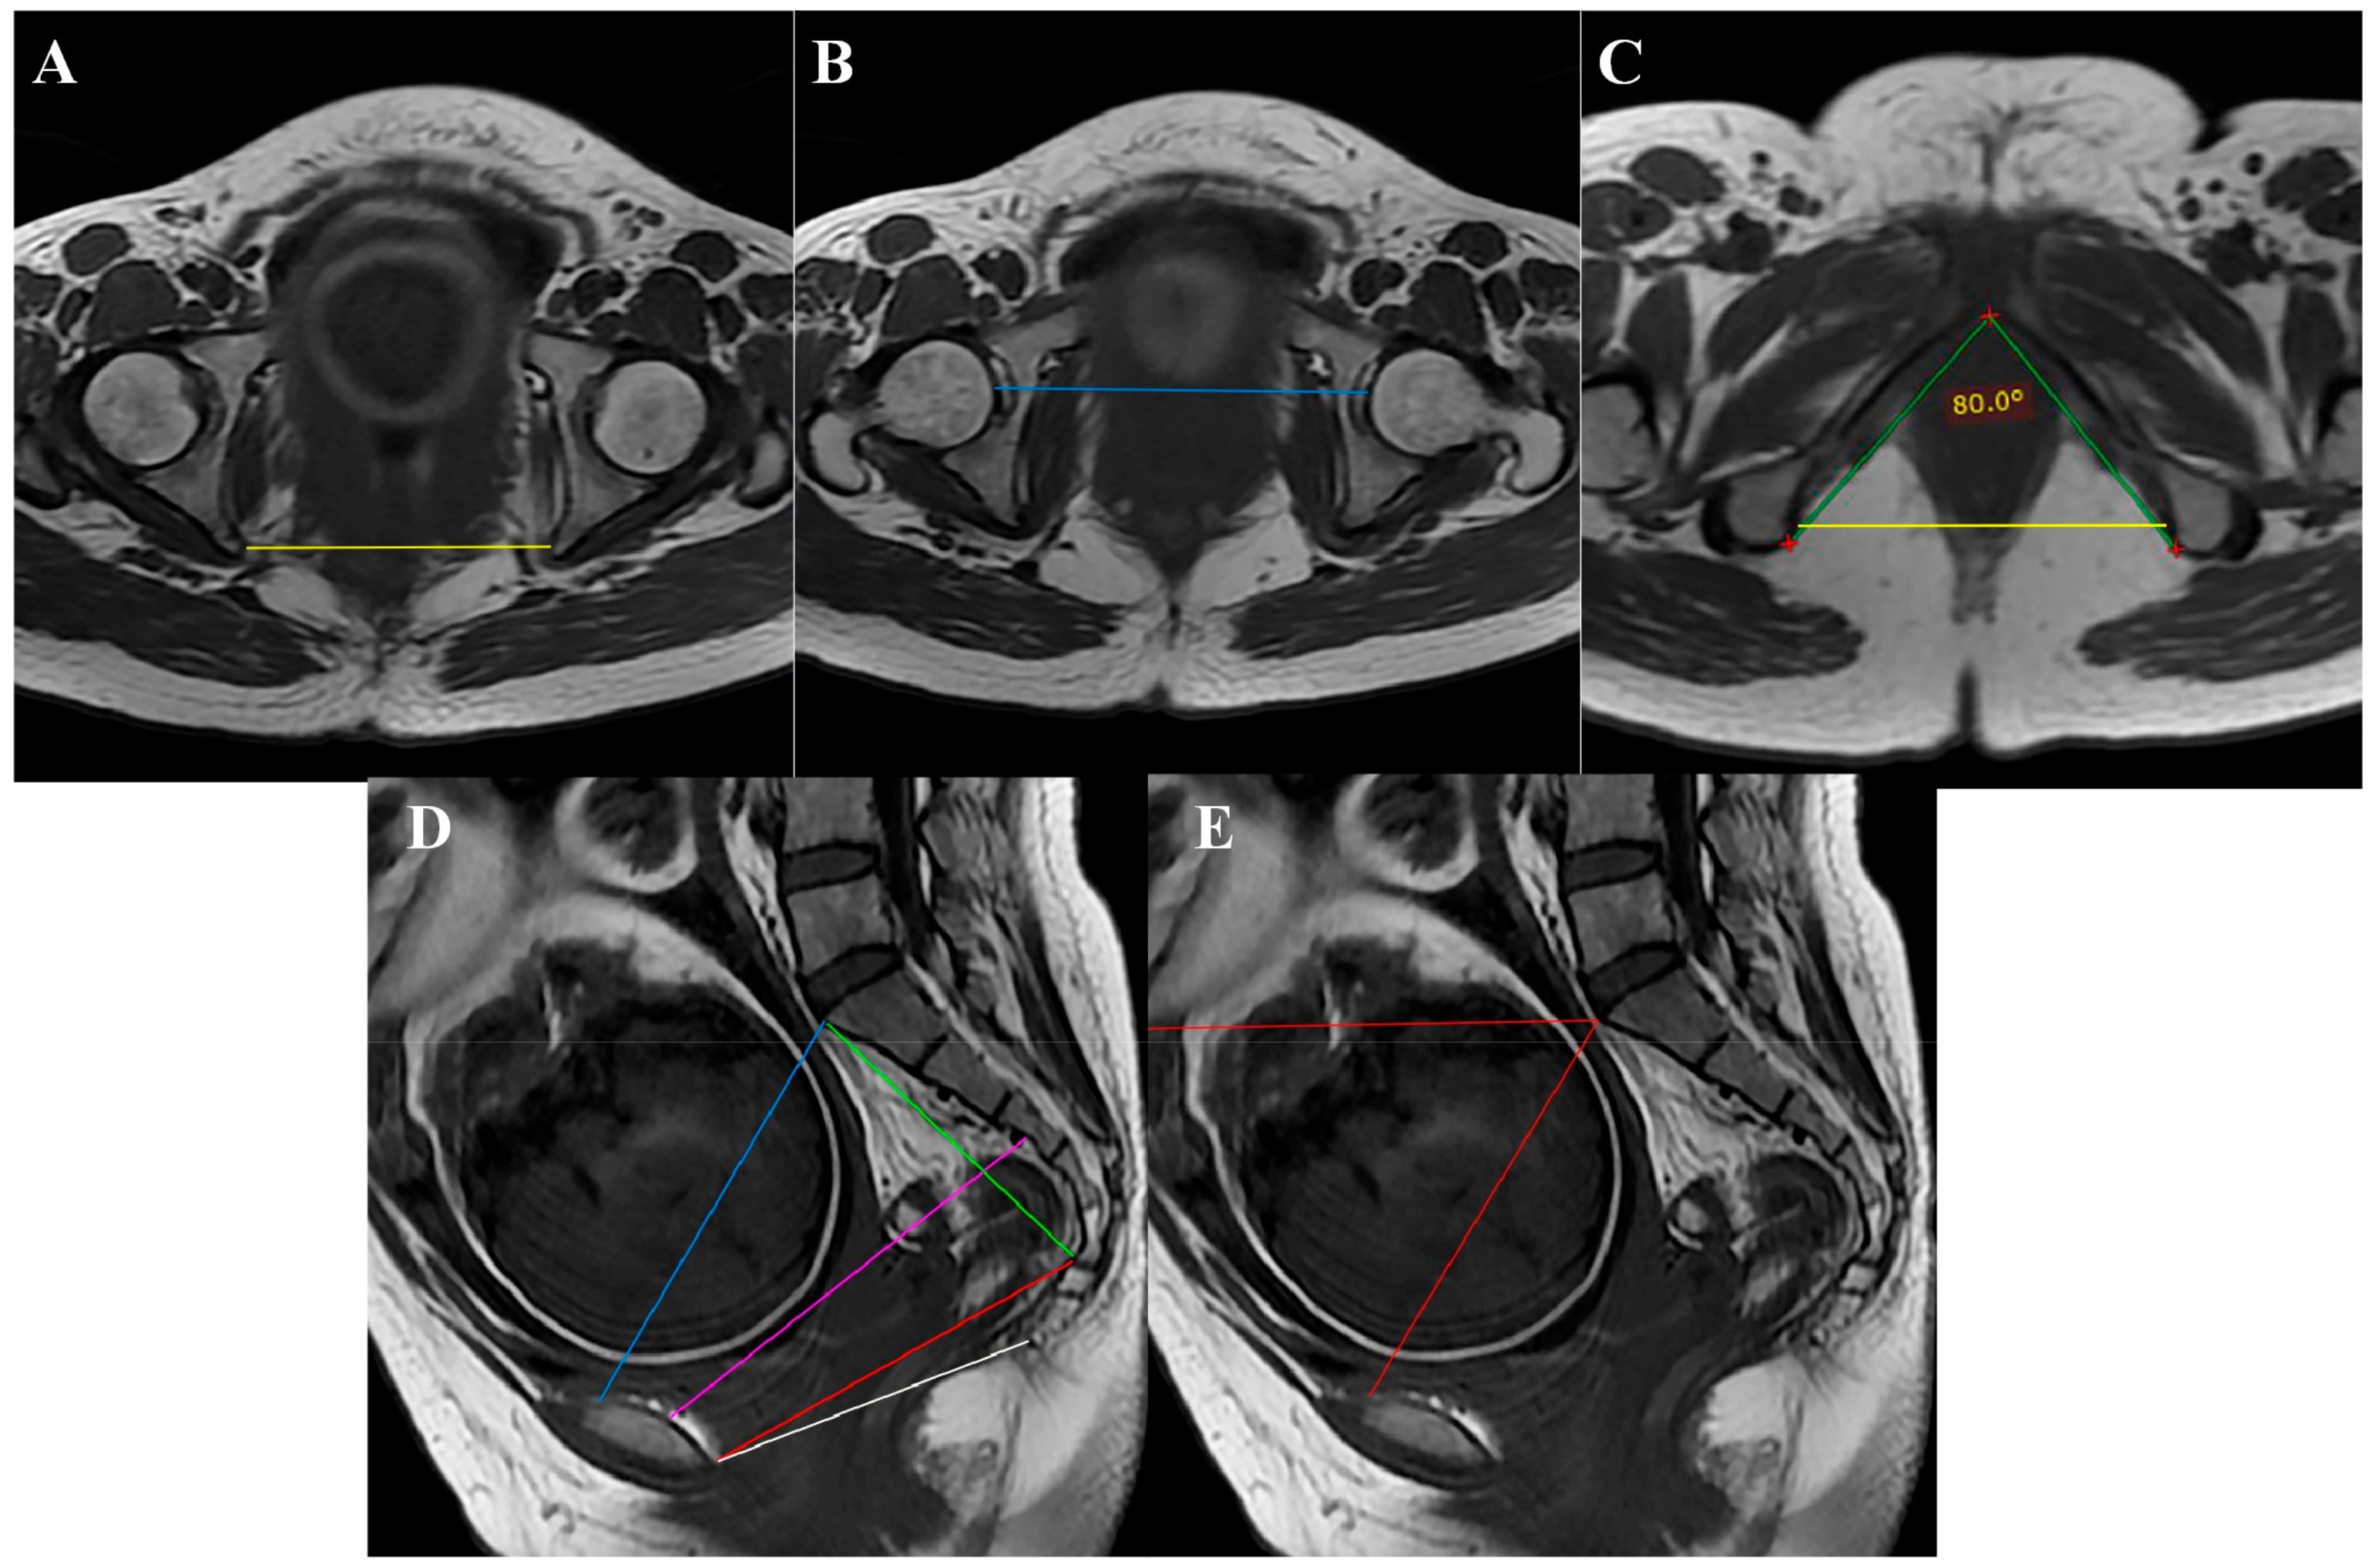

MRI pelvimetry measurements included the obstetric conjugate, intertuberous distance (ITD), interspinous diameter (ISD), pubic angle, pelvic width, bilateral acetabulum distance, sacral outlet diameter, coccygeal pelvic outlet, sacral length, and pelvic inclination (Figure 2). The fetal size was determined by the last prenatal ultrasound done within one week before expected date of delivery. The data on maternal and fetal outcomes and duration of labour were also collected.

Figure 2. MRI pelvimetry: (A) Intertuberous distance; (B) Bilateral femoral head distance; (C) Pubic angle (green line) and interspinous distance (yellow line); (D) Obstetric conjugate (blue line), pelvic width (purple line), sacral outlet diameter (red line), outlet diameter of the pelvis (white line), and sacral length (green line); (E) Pelvic inclination (red line).